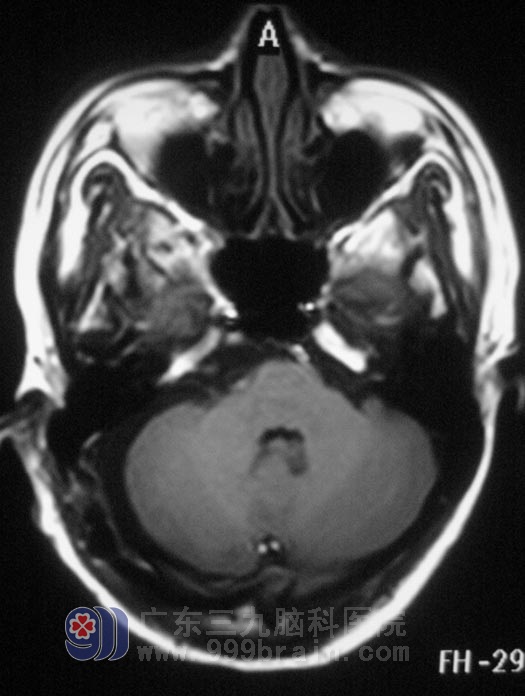

鲁明主任通过MR弥散检查,考虑胆脂瘤可能。1月4日在全麻下行右侧乙状窦后入路桥小脑角区胆脂瘤切除术,术中见白色珍珠样肿瘤组织,位于右侧桥小脑角,质软,血供丰富,显微镜下分块切除,肿瘤与三叉神经粘连紧密,小心分离后完整保留三叉神经;术中对面神经、听神经保护完好,手术顺利结束。术后一小时,小张醒后诉右侧颜面部放电样疼痛消失。没有出现面瘫、嘴角歪斜等术后并发症。术后病理结果为:胆脂瘤。

▲手术后